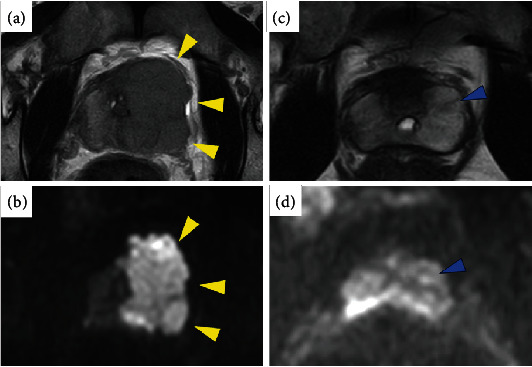

导言:针对年轻患者转移至前列腺的恶性肿瘤的治疗证据很少。在此,我们将介绍一例睾丸癌前列腺转移的病例,患者在接受诱导化疗后接受了机器人辅助前列腺癌根治术。病例介绍。患者是一名 34 岁的男性,两年前因左侧睾丸肿瘤接受了根治性睾丸切除术,被诊断为混合性生殖细胞肿瘤。他在没有辅助治疗的情况下接受了随访,但排尿困难的症状使他怀疑患上了前列腺肿瘤,经前列腺活检确诊为前列腺精原细胞瘤。经过四个周期的化疗,肿瘤标志物恢复正常,影像学显示肿瘤缩小,他接受了机器人辅助前列腺癌根治术。治疗九个月后未发现复发:结论:对于有睾丸癌病史并伴有下尿路症状的男性,考虑前列腺复发转移非常重要。

Introduction: Treatment evidence for malignancies metastatic to the prostate in young patients is scarce. Herein, we present a case of prostatic metastasis from testicular cancer treated with induction chemotherapy followed by robot-assisted radical prostatectomy. Case Presentation. The patient is a 34-year-old male who underwent radical orchiectomy for a left testicular tumor two years ago and was diagnosed with a mixed germ cell tumor. He was followed up without adjuvant therapy, but symptoms of dysuria lead to suspicion of a prostate tumor, which was diagnosed by prostate biopsy as seminoma of the prostate. After four cycles of chemotherapy, normalization of tumor markers, and tumor shrinkage on imaging, he underwent robot-assisted radical prostatectomy. No recurrence has been observed nine months after treatment.

Conclusion: In men with a history of testicular cancer presenting with lower urinary tract symptoms, it is important to consider recurrent prostate metastases.